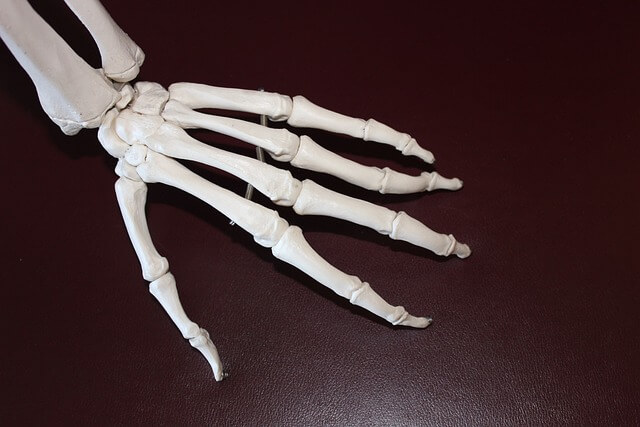

손가락 관절염, 손가락 관절 통증, 손가락 염증, 엄지 손가락 마디 통증, 손마디 통증, 손가락터널증후군 등 여러 가지 문제들이 손가락의 움직임을 제한하고 일상생활에 큰 불편을 초래합니다.

퇴행성 손가락 관절염은 손가락 끝마디에 주로 발생하며, 연골이 닳아 염증이 생기는 질환입니다.

관절염은 관절의 염증을 일으켜 통증과 부기를 초래하며, 손가락 끝마디가 굵어지고 돌출되는 특징이 있습니다.